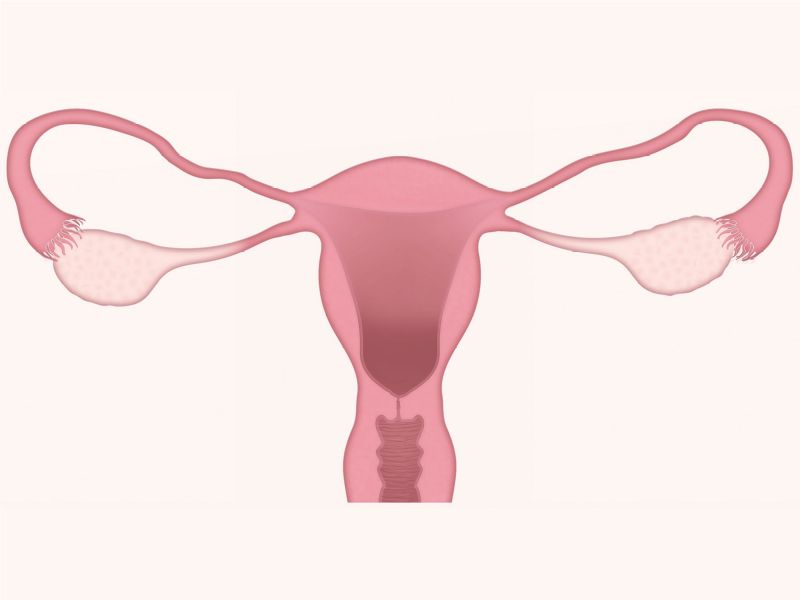

Ovary

- Capsule covered by modification of peritoneum

- Called germinal epithelium

- Simple squamous/cuboidal

- Subdivided

- Not clearly defined

- Cortex - contains ovarian follicles

- Medulla - vascular

Uterus

3 regions3 layers

Three regions

FundusBody

Cervix

Three layers

- Endometrium

- Formation placenta

- Myometrium

- Enlarge during pregnancy

- Expulsion fetus & placenta

- Adventitia